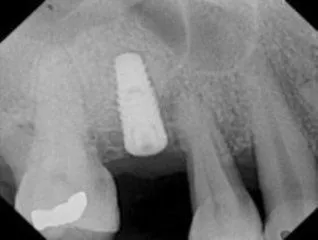

Implant Placement with Bone Graft

Before

After